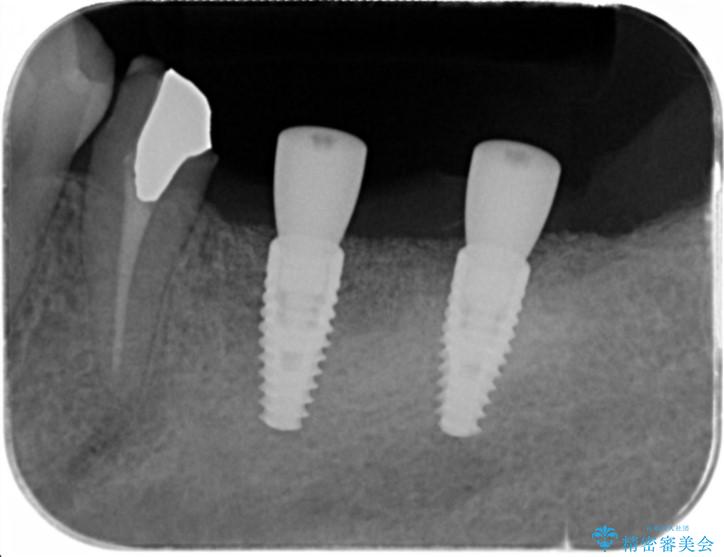

遊離歯肉移植術を併用した、破折歯のインプラント治療

- 他院で根の治療まで終え、違和感が取れず相談に来院されました。

当該歯を精査したところ、歯根に破折が見られ抜歯を余儀なくされました。

抜歯後、インプラントを用いて咬合機能を回復すると共に周囲に強固な角化歯肉を移植することによりより長期にわたり安定したインプラント周囲環境となるよう治療を計画します。

- 83.6万円(インプラント×2・アバットメント×2・クラウン×2)費用は治療当時の料金となります